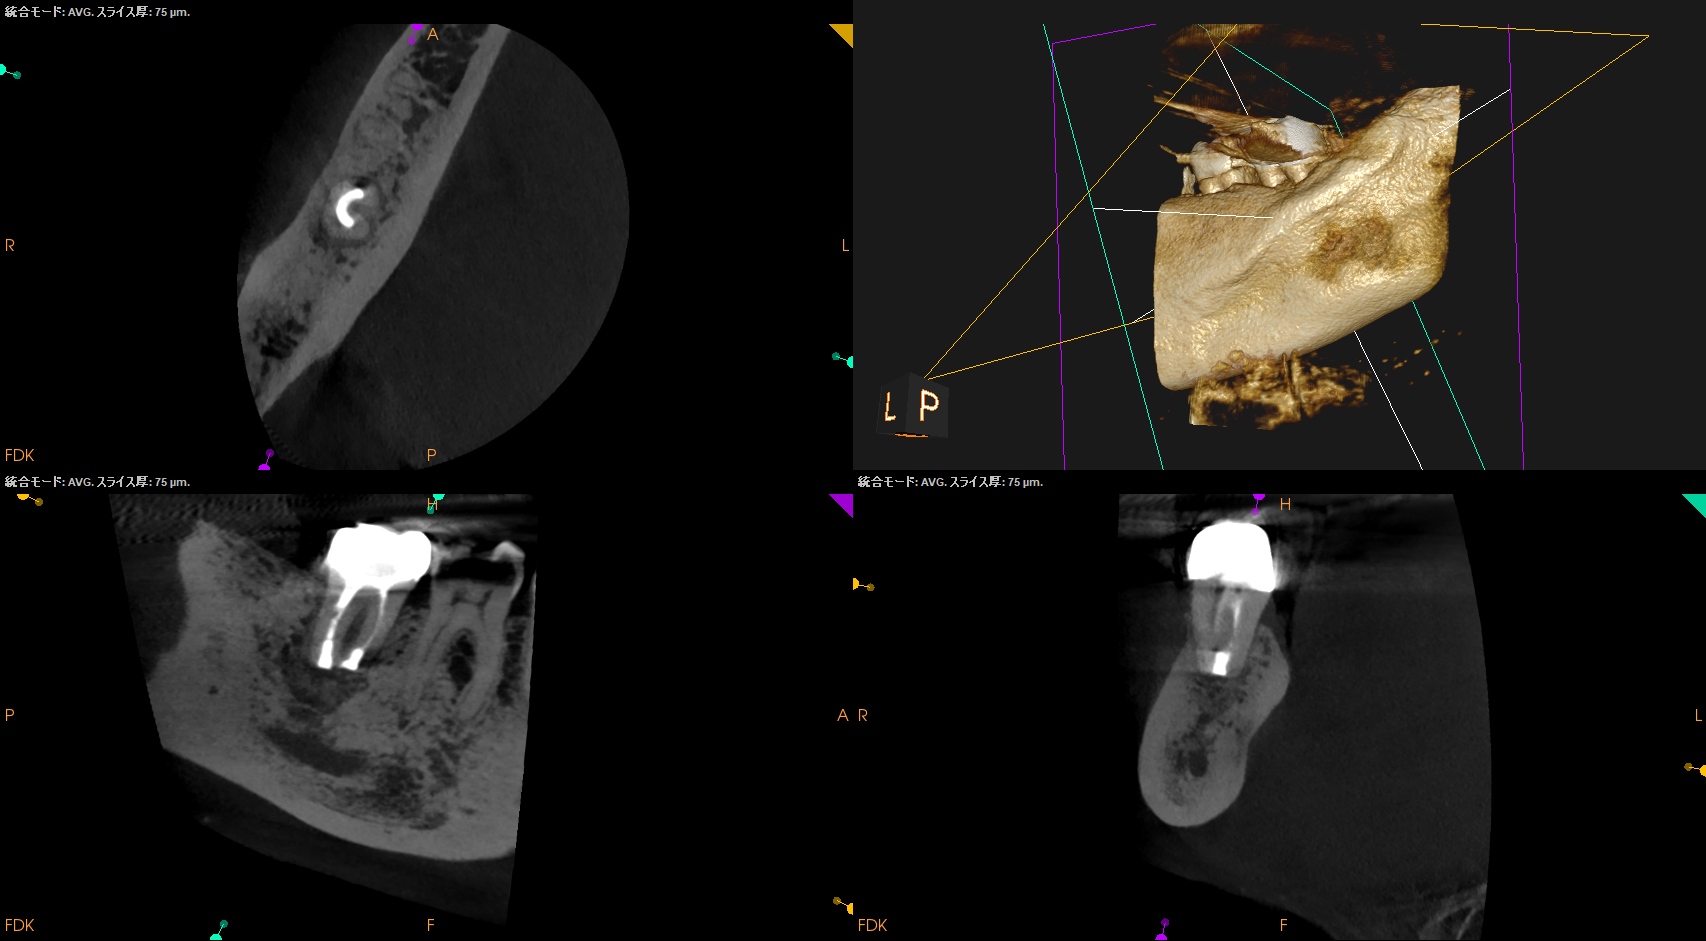

#31 Intentional Replantation 6M recall(2025.12.17)

PA所見も半年前とは大違いである。

Sinus tractは消失し歯槽骨も大幅に回復し、最終補綴も装着されている。